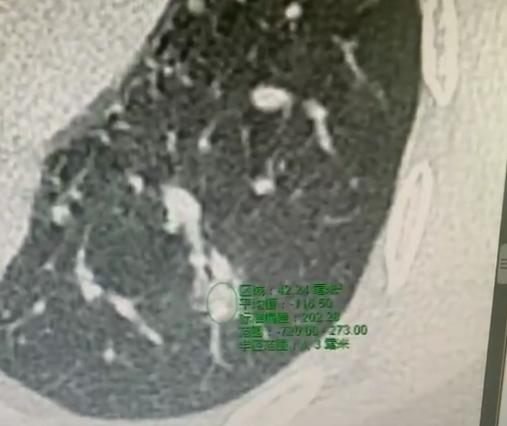

肺部结节长到多大才是恶性,才需要做手术呢?其实这不是一个很正确的认知,肺部结节到底是不是恶性,并不是根据它长到多大才变成恶性的,而是结节增大本身这个行为提示恶性的概率大,也就是说结节如果永远不变化的话,说明它里面细胞不会增生,不会复制,肿瘤只要产生了,大概率不会呆着不动,它始终会有一天会增大的。 另外结节变大的速度,对结节良恶性的判断也有一定的影响,如果结节短时间内迅速的增大,比如说一个星期就长大一倍,这个基本上可以排除恶性的可能性,因为肺部肿瘤的生长都有一定的规律。那种渐进性逐渐增大的结节更有可能是恶性,比如说去年是5毫米,今年长到8毫米,明年长到了1.5厘米,那么恶性的概率就非常大。如果是一个星期之前是5毫米,一个星期之后变成两厘米,那肯定就不是恶性,因为恶性长得没那么快。通常是良性,比如说感染性结节长得更加快一点,符合这种一星期涨几倍的规律。 还有一个规律,就是肺部恶性结节不可能逆转性的缩小,如果一个结节缩小了,那肯定不是恶性,所以这个世界上没有能够消掉恶性结节的药物,如果结节是恶性的话,就不要妄想通过药物把它缩小或者消除了。结节 肺部结节